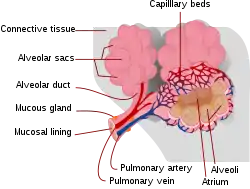

Interstitial lung disease (ILD), or diffuse parenchymal lung disease (DPLD),[3] is a group of respiratory diseases affecting the interstitium (the tissue) and space around the alveoli (air sacs) of the lungs.[4] It concerns alveolar epithelium, pulmonary capillary endothelium, basement membrane, and perivascular and perilymphatic tissues. It may occur when an injury to the lungs triggers an abnormal healing response. Ordinarily, the body generates just the right amount of tissue to repair damage, but in interstitial lung disease, the repair process is disrupted, and the tissue around the air sacs (alveoli) becomes scarred and thickened. This makes it more difficult for oxygen to pass into the bloodstream. The disease presents itself with the following symptoms: shortness of breath, nonproductive coughing, fatigue, and weight loss, which tend to develop slowly, over several months. The average rate of survival for someone with this disease is between three and five years.[5] The term ILD is used to distinguish these diseases from obstructive airways diseases.

Prolonged ILD may result in pulmonary fibrosis, but this is not always the case. Idiopathic pulmonary fibrosis is interstitial lung disease for which no obvious cause can be identified (idiopathic) and is associated with typical findings both radiographic (basal and pleural-based fibrosis with honeycombing) and pathologic (temporally and spatially heterogeneous fibrosis, histopathologic honeycombing, and fibroblastic foci).